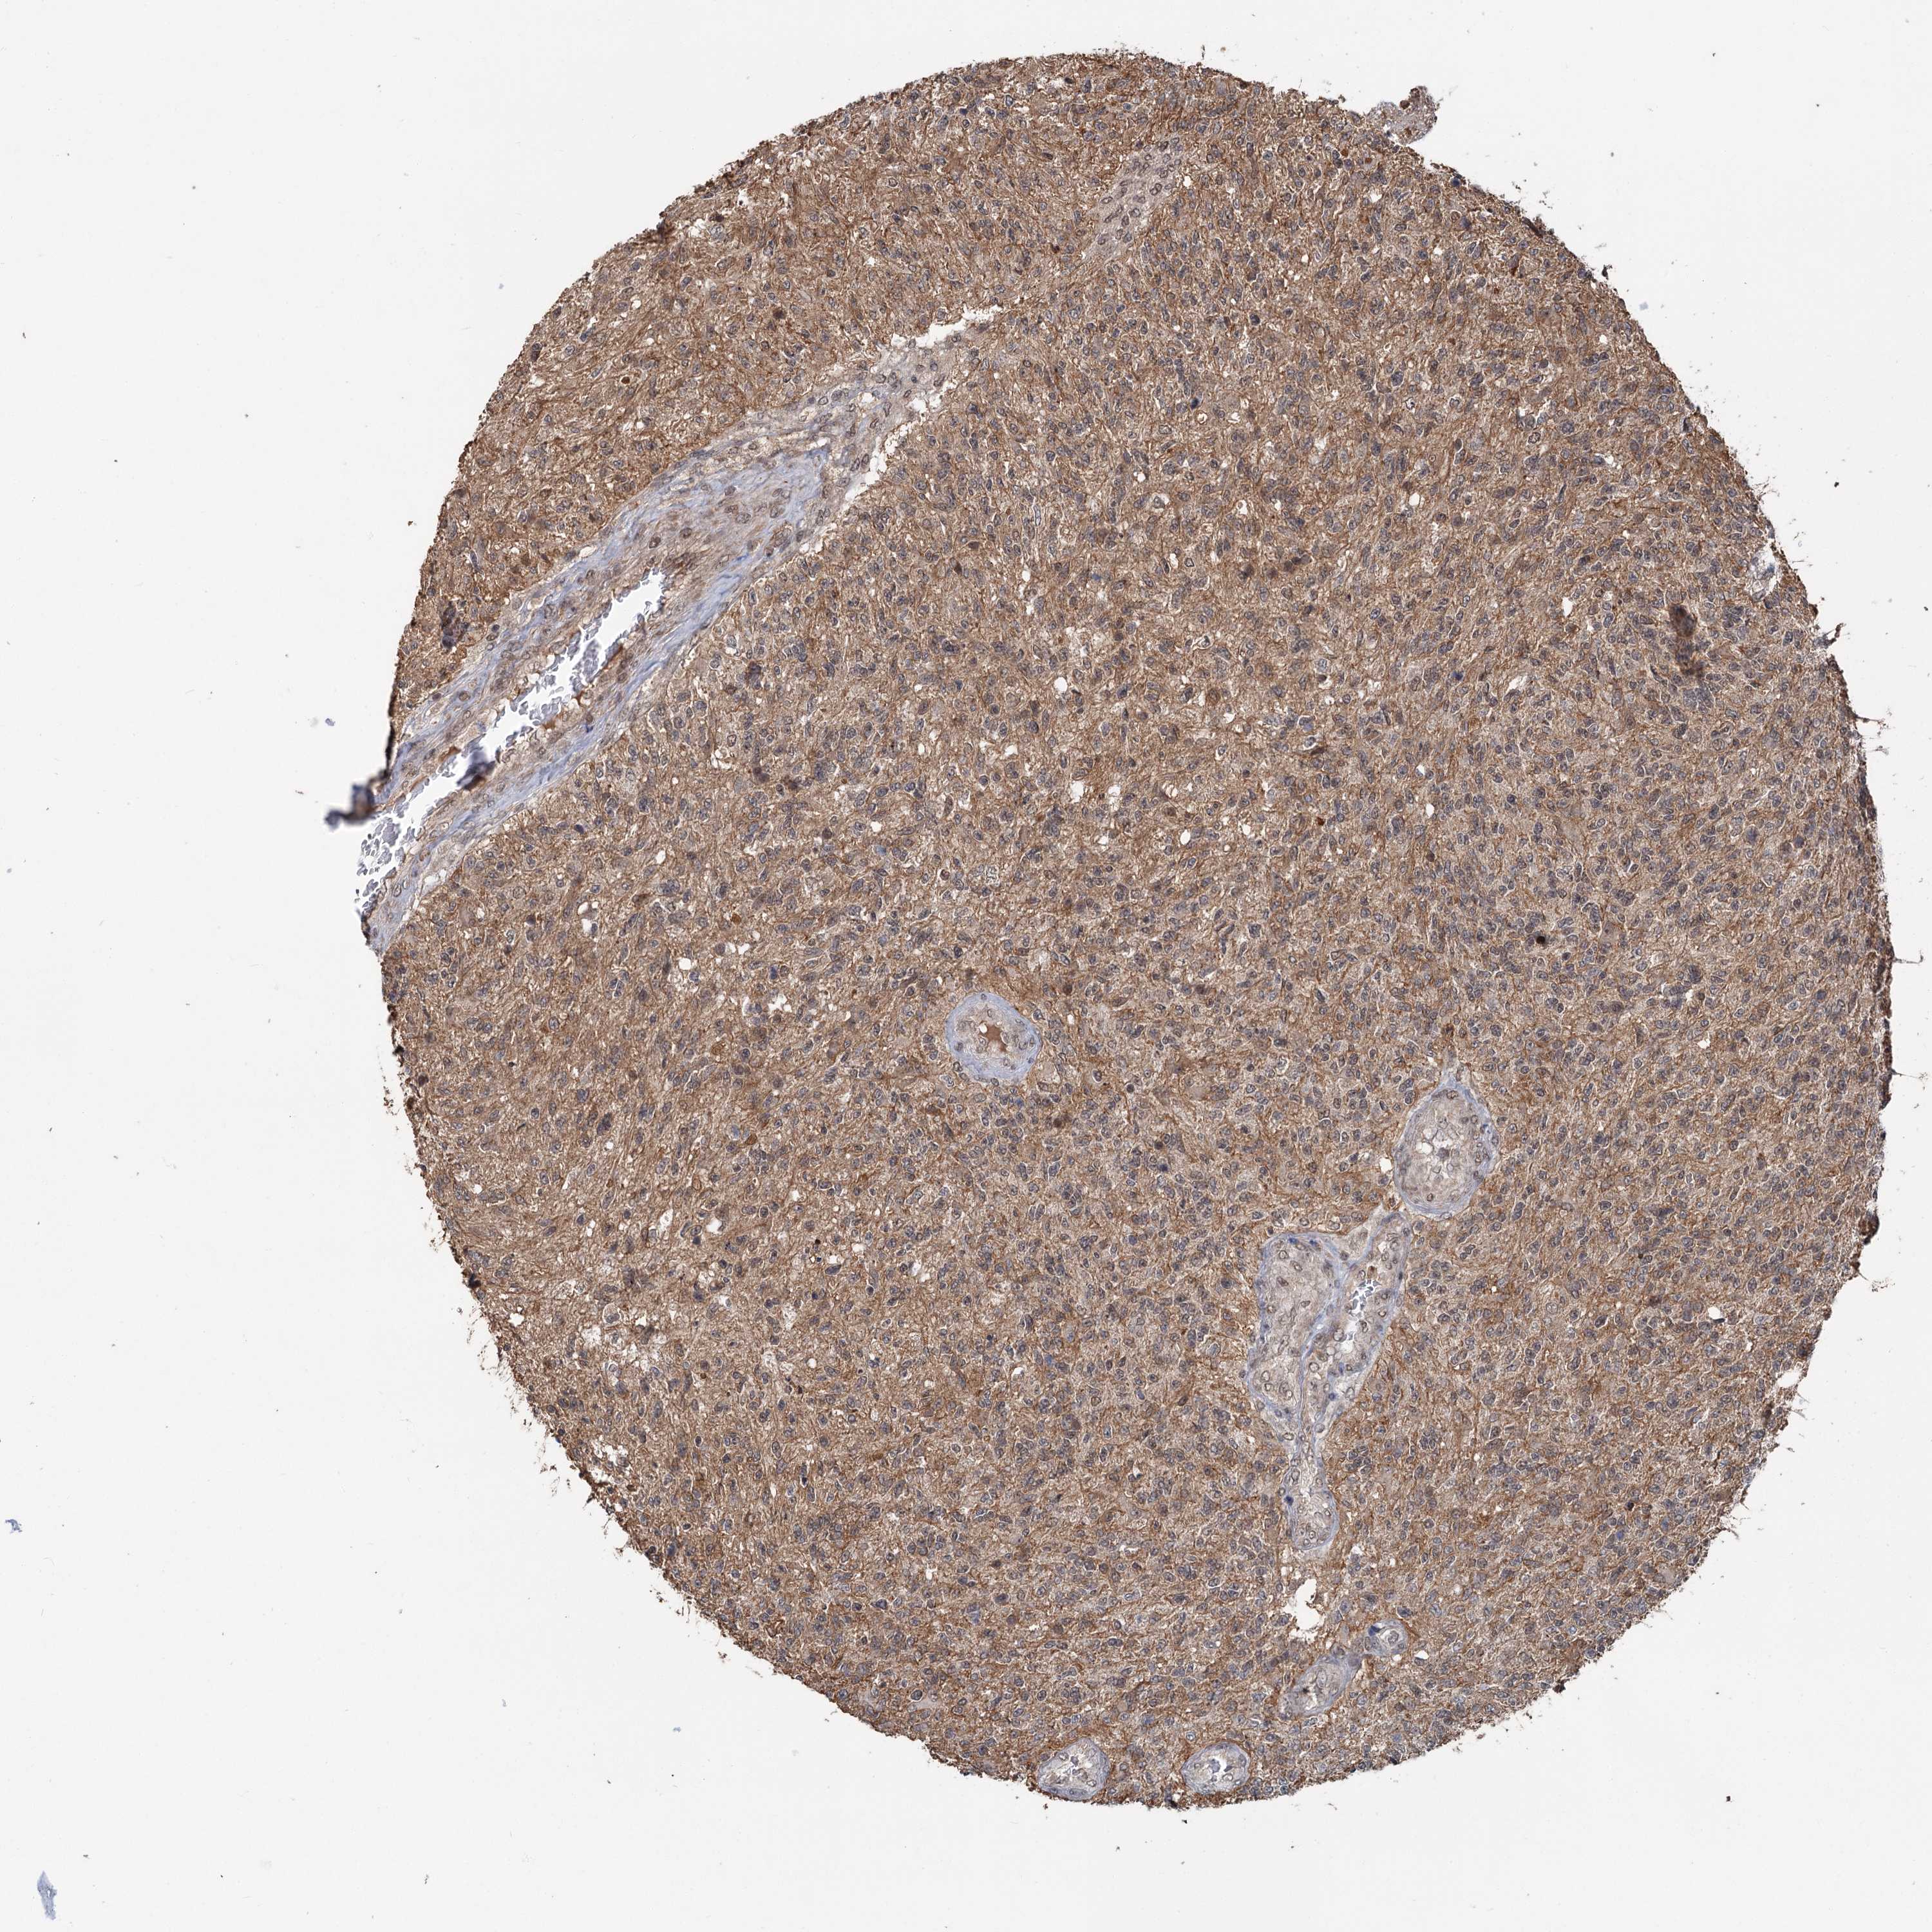

GLIOMA - Protein expressioni

A mouse-over function shows sample information and annotation data. Click on an image to view it in a full screen mode. Samples can be filtered based on level of antibody staining by selecting one or several of the following categories: high, medium, low and not detected. The assay and annotation is described here.

Note that samples used for immunohistochemistry by the Human Protein Atlas do not correspond to samples in the TCGA dataset.

Antibody stainingi

Antibody staining in the annotated cell types in the current human tissue is reported as not detected, low, medium, or high, based on conventional immunohistochemistry profiling in selected tissues. This score is based on the combination of the staining intensity and fraction of stained cells.

Each image is clickable and will lead to virtual microscopy that enables deeper exploration of all samples and also displays staining intensity scores, fraction scores and subcellular localization as well as patient and tissue information for each sample.

Antibody HPA038497

Antibody HPA038498

Staining

High

Medium

Low

Not detected

Intensity

Strong

Moderate

Weak

Negative

Quantity

>75%

75%-25%

<25%

None

Location

Nuclear

Cytoplasmic/membranous

Cytoplasmic/membranous,nuclear

Glioma, malignant, High grade

Glioma, malignant, Low grade